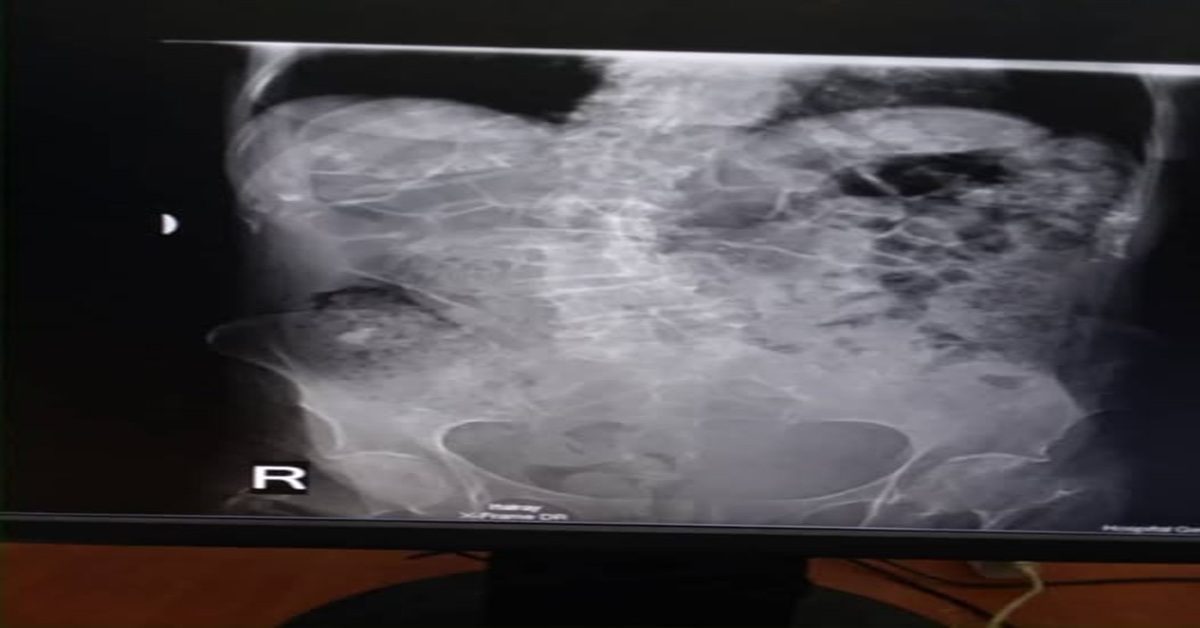

Los médicos de guardia, al ver una simple radiografía, diagnosticaron a la ligera una “úlcera perforada” y dijeron que había que operar de urgencia.

Desde el análisis médico de la imagen, no hay evidencia de neumoperitoneo, ni signos de perforación gástrica. La placa muestra asas intestinales distendidas, compatibles con íleo paralítico o fecaloma, no con una emergencia quirúrgica.

La conducta debió ser otra: manejo conservador, hidratación, TAC abdominal, seguimiento clínico. Pero en lugar de medicina, recibió improvisación. En lugar de cuidados, la trataron como un estorbo.